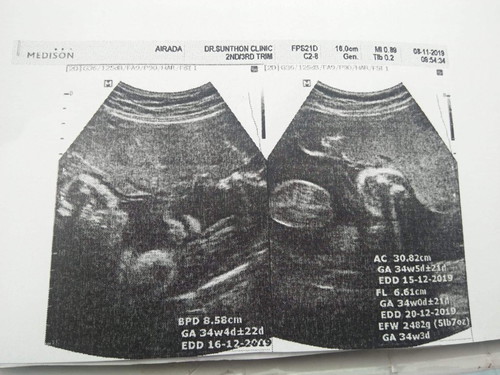

เมื่อวานไปหาคุณหมอตามนัดมา ซาวด์ดูน้อง คุณหมอบอกน้องน้ำหนักประมาณ 2500 (เค้าจะประเมินจากเครื่องซาวด์ ส่วนในเครื่องซาวด์ 2482 เพราะในเครื่องซาวด์34วีคแต่จริงๆ 36 วีคแล้ว น้ำหนักน้องจริงๆจะเยอะกว่าที่เครื่องซาวด์กับที่คุณหมอบอกใช่ไหมคะ กลัวน้องจะน้ำหนักน้อยไม่แข็งแรง